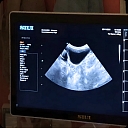

Terion, LTD, Veterinary clinic

Laboratorijas 2A, Rīga, LV-1012

Laboratory examinations with a microscope in a veterinary clinic